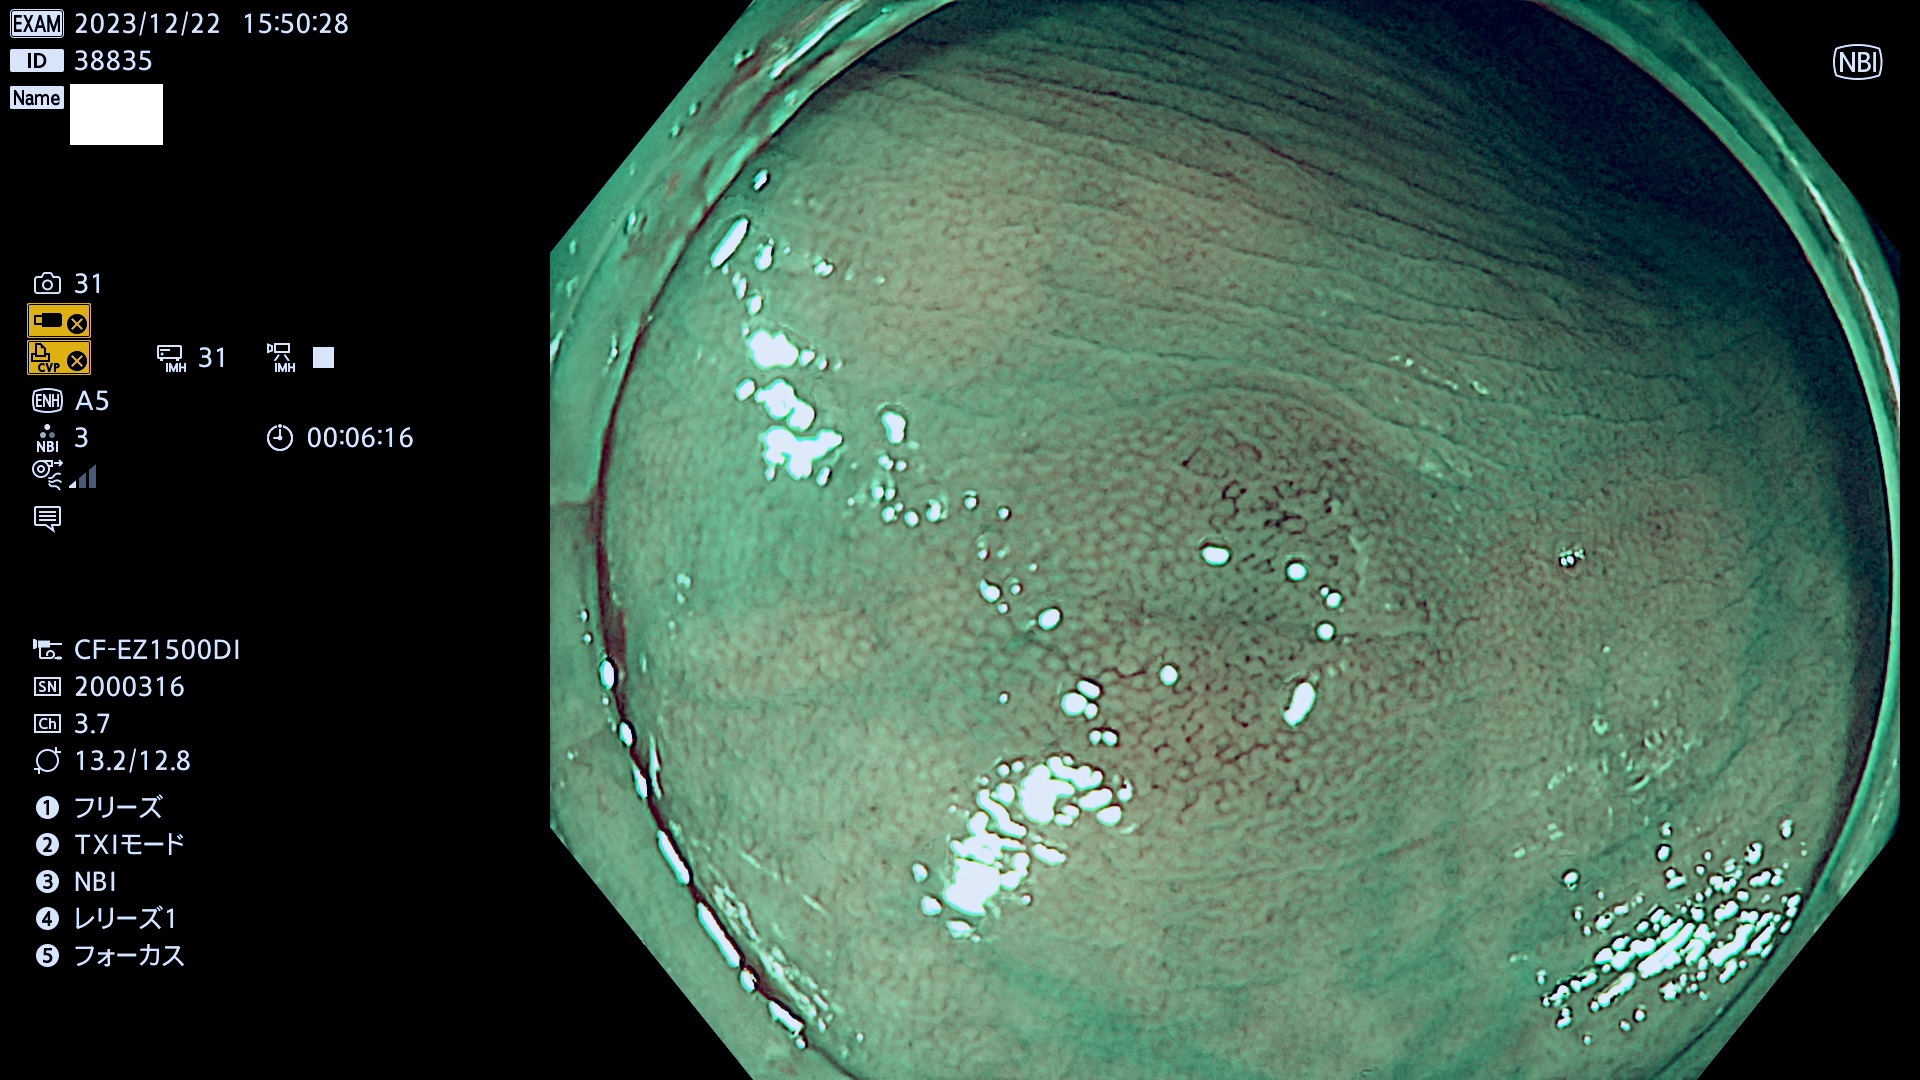

表面型腺腫(Flat Adenoma)の中で、完全に平坦な物をUb、陥凹している物をUcと呼びます。平坦隆起型(Ua)よりも、発見が難しく危険な病変です。

当院で見つかった、炎症(ビラン)と極めて紛らわしい腺腫の例